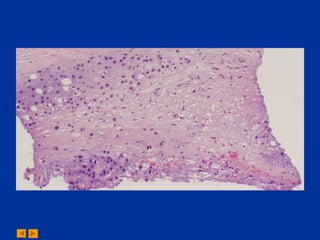

A 36-year-old female presented with a left popliteal mass. The differential diagnosis for the fine needle aspiration of the mass included chondroma and chondrosarcoma. The diagnosis from the cytopathology conference was chondrosarcoma.